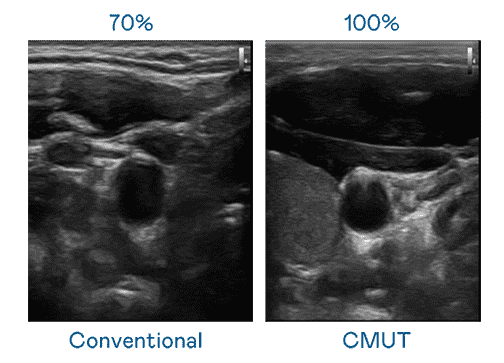

CMUT 技术是一种用电容式微机电元件来产生超音波讯号的技术。。。。与传统 PZT 压电式技术相比,,,CMUT 频宽增加 30%,,,更宽频的超音波讯号让影像解析度大幅提升,,,,是实现高影像品质医疗超音波扫描、、促进精准医疗发展的关键技术。。。

大频宽带来超清晰影像

超音波影像的解析度高低,,,首先取决于探头能发出的讯号频宽。。。尊龙集团 CMUT 可提供高清晰的超音波讯号,,,,提供高频宽、、、、高灵敏度、、影像纹理细节更高的超音波影像,,,协助医护人员缩短影像判读时间及利用精准的医疗影像进行诊断。。。